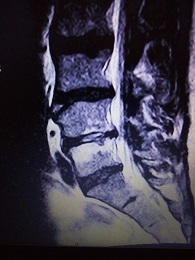

ich hatte vor kurzen ein Kontroll-MRT-LWS, weil bei mir eine Bandscheibenentzündung in DD oder eine Wirbelkörperentzündung. Im Bild im L4/5 ist dort etwas ungewöhnliches zu sehen, was kann das sein?

habe noch paar Bilder gefunden, die in der Sequenz T2W TSE sag; T1W TSE sag; TIR long TE cor

- Bild1.jpg (80.48 KiB) 6503 mal betrachtet

- Bild2.jpg (81.92 KiB) 6503 mal betrachtet

- Bild3.jpg (92.15 KiB) 6503 mal betrachtet

- Bild4.jpg (97.57 KiB) 6503 mal betrachtet

Das mit dem Kontroll-MRT kam auch nur von der HÄ, weil das ein Neurologe empfohlen hat. Weil voriges Jahr in der Stelle L4/5 eine Vermutung geäußert wurde, das im DD eine Diszitis vorliegt und das nach einem Jahr ein Verlaufs-MRT gemacht werden soll.